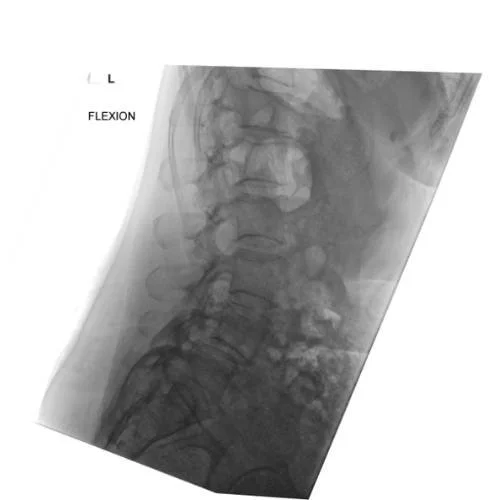

X-ray of Bertolotti Syndrome

Dynamic X-ray: Taken in flexion to assess spinal movement and check for instability. This helped confirm that surgery was necessary to stabilise the segment.